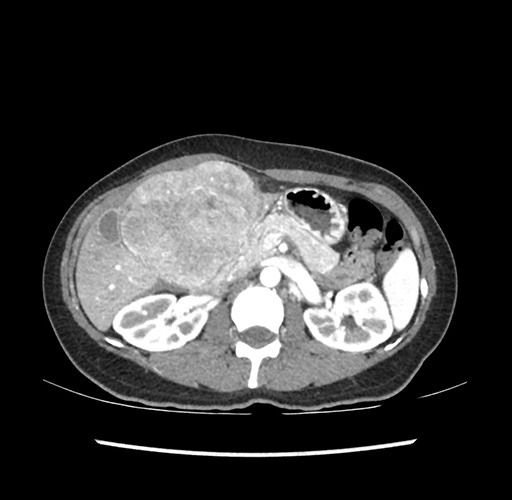

Imaging Analysis

Look through the patient's CT scan to identify any areas of concern for the necessary procedure.

Based on your CT findings, which issue(s) would give reason for "planned slowing down moment(s)" in this case?

Considering a standard left lateral sectionectomy procedure, what step(s) of the operation would you do differently in this case ?